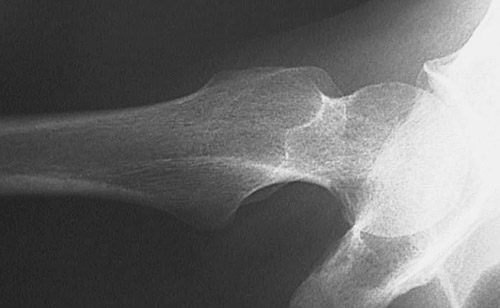

The femur seen here with the hip at the right demonstrates severe osteoporosis with marked loss of bone density.